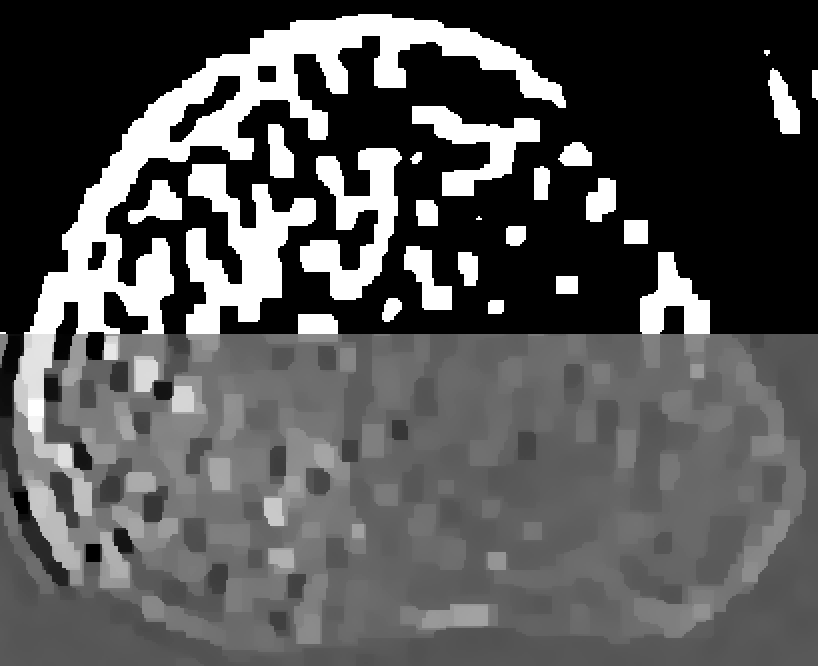

Refer to captionID blurfullRefer to captionshort-1Refer to captionshort-2Refer to captionSI blurRefer to captionRefer to captionRefer to captionSV blurRefer to captionRefer to caption0.0000.0150.0300.0450.060

Figure 4: Reconstructions of the medial bone with the highest mutual overlap over all thresholds and β𝛽\beta’s. The top half of each reconstruction is thresholded.

Figure 4 shows the medial-bone reconstructions (bottom of each image) and segmentations (top of each image) corresponding to the best possible mutual overlap (optimal threshold and β𝛽\beta values) with each scan type and blur model combination. All SV reconstructions depict more trabecular structure than the shift-invariant (SI) or ID models. The difference in image quality among ID reconstructions is readily apparent in these images, with the short-1 scan resulting in the most trabecular detail. Finally, the SI images depict more detail than the ID model but less detail than the SV reconstructions. However, the SI model results in a ringing artifact, particularly evident on the lower left aspect of the medial bone in the full scan reconstruction. This is likely due to blur/model mismatch (the SI model is accurate at the center of the detector but less accurate at the edges).